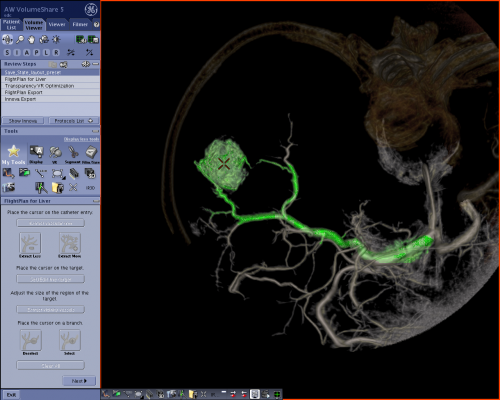

GE Healthcare’s FlightPlan for Liver helps interventionalists plan their liver embolization procedures. The physician simply needs to select the tip of the catheter and a hypervascular tumor on a 3-D image, and let the software highlight the vessels traveling from the catheter to the lesion’s vicinity. The highlighted vessels can then be used as a 3-D roadmap with the Innova Vision application, and superimposed on the live fluoroscopic image to help the doctor guide the catheter into the target artery.

“The development of this technology for liver embolization is a great example of how collaborative work between physicians and engineers can help cancer patients. In three simple steps, the interventional radiologist can untangle the complex tumor vessels in the liver to immediately demonstrate which vessels feed the liver cancer and require catheter directed treatment,” said Stephen B. Solomon, chief of Interventional Radiology Service, Memorial Sloan-Kettering Cancer Center.